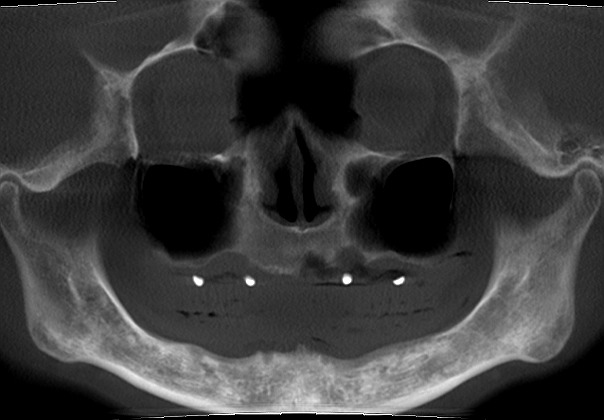

下顎管神経がすぐそこまで出てるためインプラント埋入には最新の注意を

埋入前、埋入後のスカル

下顎管神経に気を付けながら埋入していきます

安全に配置取りして埋入しました